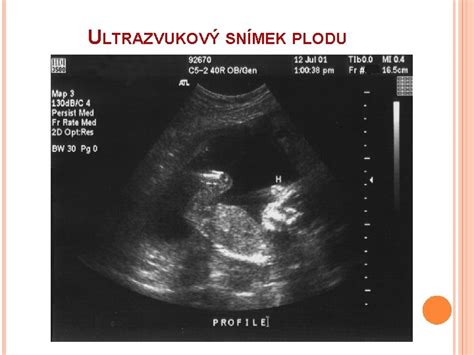

V druhom trimestri je dôležité nezabudnúť na registráciu do pôrodnice. Niektoré pôrodnice vyžadujú registráciu už v skoršom štádiu tehotenstva, preto je dobré si tieto termíny včas overiť. Medzi 20. až 22. týždňom tehotenstva sa vykonáva morfologický ultrazvuk, známy aj ako "veľký ultrazvuk", ktorý detailne zobrazuje anatómiu plodu. Medzi 24. až 28. týždňom vás čaká glukózový tolerančný test (OGTT) na vylúčenie tehotenskej cukrovky. V rozmedzí 24. až 30. týždňa je tiež ideálny čas na absolvovanie 3D alebo 4D ultrazvuku, ktorý vám umožní vidieť vaše bábätko v realistickejších rozmeroch.

- Morfologický ultrazvuk: Medzi 20. až 22. týždňom.

- 3D/4D ultrazvuk: Ideálne medzi 24. až 30. týždňom.

V ktorých týždňoch tehotenstva sa robí 3D alebo 4D ultrazvuk?Ideálna doba na tieto ultrazvuky je medzi 24. až 30. týždňom tehotenstva, kedy je plod dostatočne vyvinutý na zobrazenie detailov.